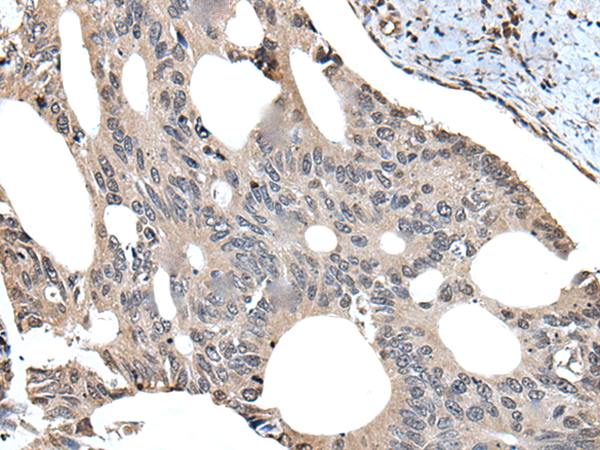

分类: 科研抗体货号: P09345别名: B4GALT; GALGT2应用: IHC反应种属: Human